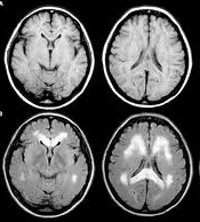

КТ головного мозга

КТ головного мозга назначают в онкологии, травматологии, неврологии и нейрохирургии, в некоторых случаях используют в гинекологии (для оценки состояния гипофиза, которая участвует в регуляции уровня гормонов) и в психиатрии с неинформацией других методов исследования. Методика используется при планировании операции, в процессе динамического наблюдения за пациентом в послеоперационном периоде, при мониторинге эффективности лечения и при оценке отдаленных результатов. Манипуляция позволяет определить местоположение патологического очага, его форму, размеры, распространенность.

Компьютерная томография головного мозга (КТ) показана пациентам с тяжелыми головными болями неизвестной этиологии, двойным зрением, головокружением и обмороком. Процедура выполняется, если есть подозрение на внутричерепное кровоизлияние после черепно-мозговой травмы, чтобы выяснить причину постоянной тошноты и рвоты во время сотрясения мозга. Во время томографии определяется место патологических изменений, отека, гематомы и смещения структур головного мозга. КТ назначают для визуализации инородных тел в ткани мозга. Оцифровка необходима у пациентов с ранее обнаруженными опухолями головного мозга, чтобы определить распространенность процесса и определить стадию рака. Используя этот метод, проводится дифференциальная диагностика объемных образований и обеспечивается контроль эффективности лечения онкологических больных.

В неврологии томография проводится при подозрении на инсульт, атеросклероз, резкое ухудшение слуха и зрения, памяти и речи, при эпилепсии и гидроцефалии. КТ головного мозга необходима для дифференциальной диагностики нейроинфекций и опухолей головного мозга, подтверждения нейродегенерации ЦНС (болезнь Паркинсона и болезнь Альцгеймера), установления причины судорог. Исследование назначают пациентам с резко неадекватным поведением, с нарушениями умственного развития для выявления «зоны полутени» у пациентов с цереброваскулярным поражением - перифокальной зоной с перфузией на предфункциональном уровне.